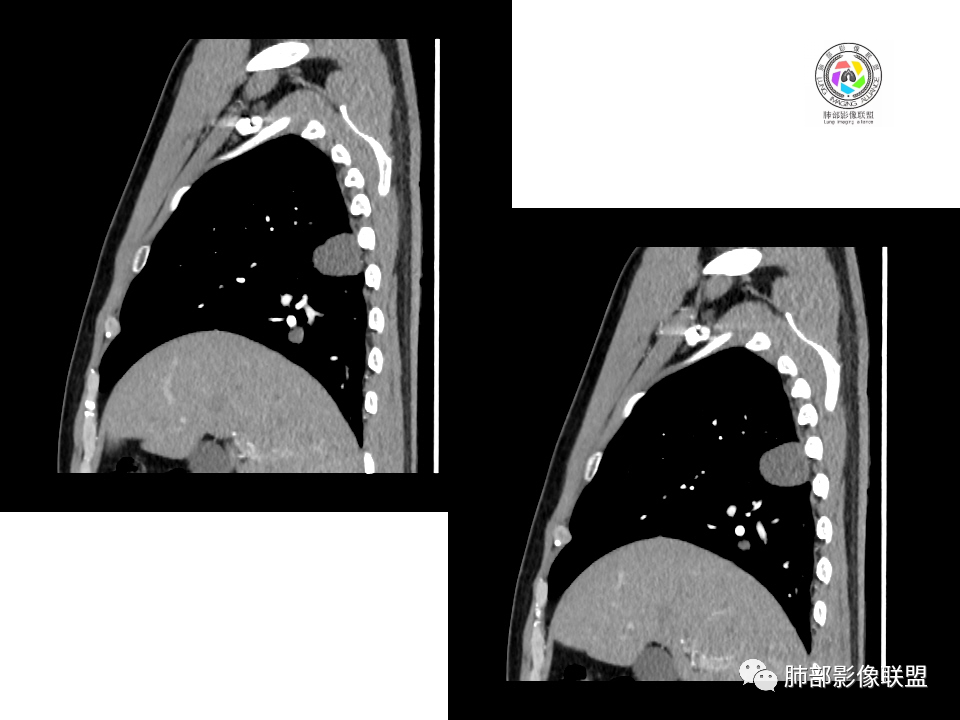

中年男性,体检发现占位。右肺下叶背段胸膜下肿块,周围晕征,有小分叶,与支气管、肺内血管关系不清,形似山丘,重建可见肿块呈D字形凸向肺部。似跨斜裂,似有小凸起与肋下缘相连,增强似有轻微均匀强化。右肺下叶外基底段小结节,位于血管周围,部分边缘平直,轻微均匀强化。考虑二元:一、右下叶背段肿块为肺外病变,神经鞘瘤?SFT?鉴别小细胞癌、隐球菌病;二、右下叶外基底段结节考虑为良性结节、炎性肉芽肿?

2.右肺下叶背段胸膜下块影,边界清楚光整,上下极见磨玻璃晕,未见明显分叶毛刺和棘状突起,未见胸膜凹陷或胸壁侵入。密度均匀,轻度不均匀强化。未见支气管进入。

4.右肺下叶基底段支气管血管束旁小结节影,边界清楚,强化不明显。注意,这结节在“遥远的”基底段。

注意,基底段支气管血管束旁的小结节影,即便是淋巴结,也与背段病灶引流途径不符。

4.良性占位绕不过去,如发生于该部位的孤立性纤维瘤等……

病灶不均匀强化可以将含液支气管囊肿排除在外。